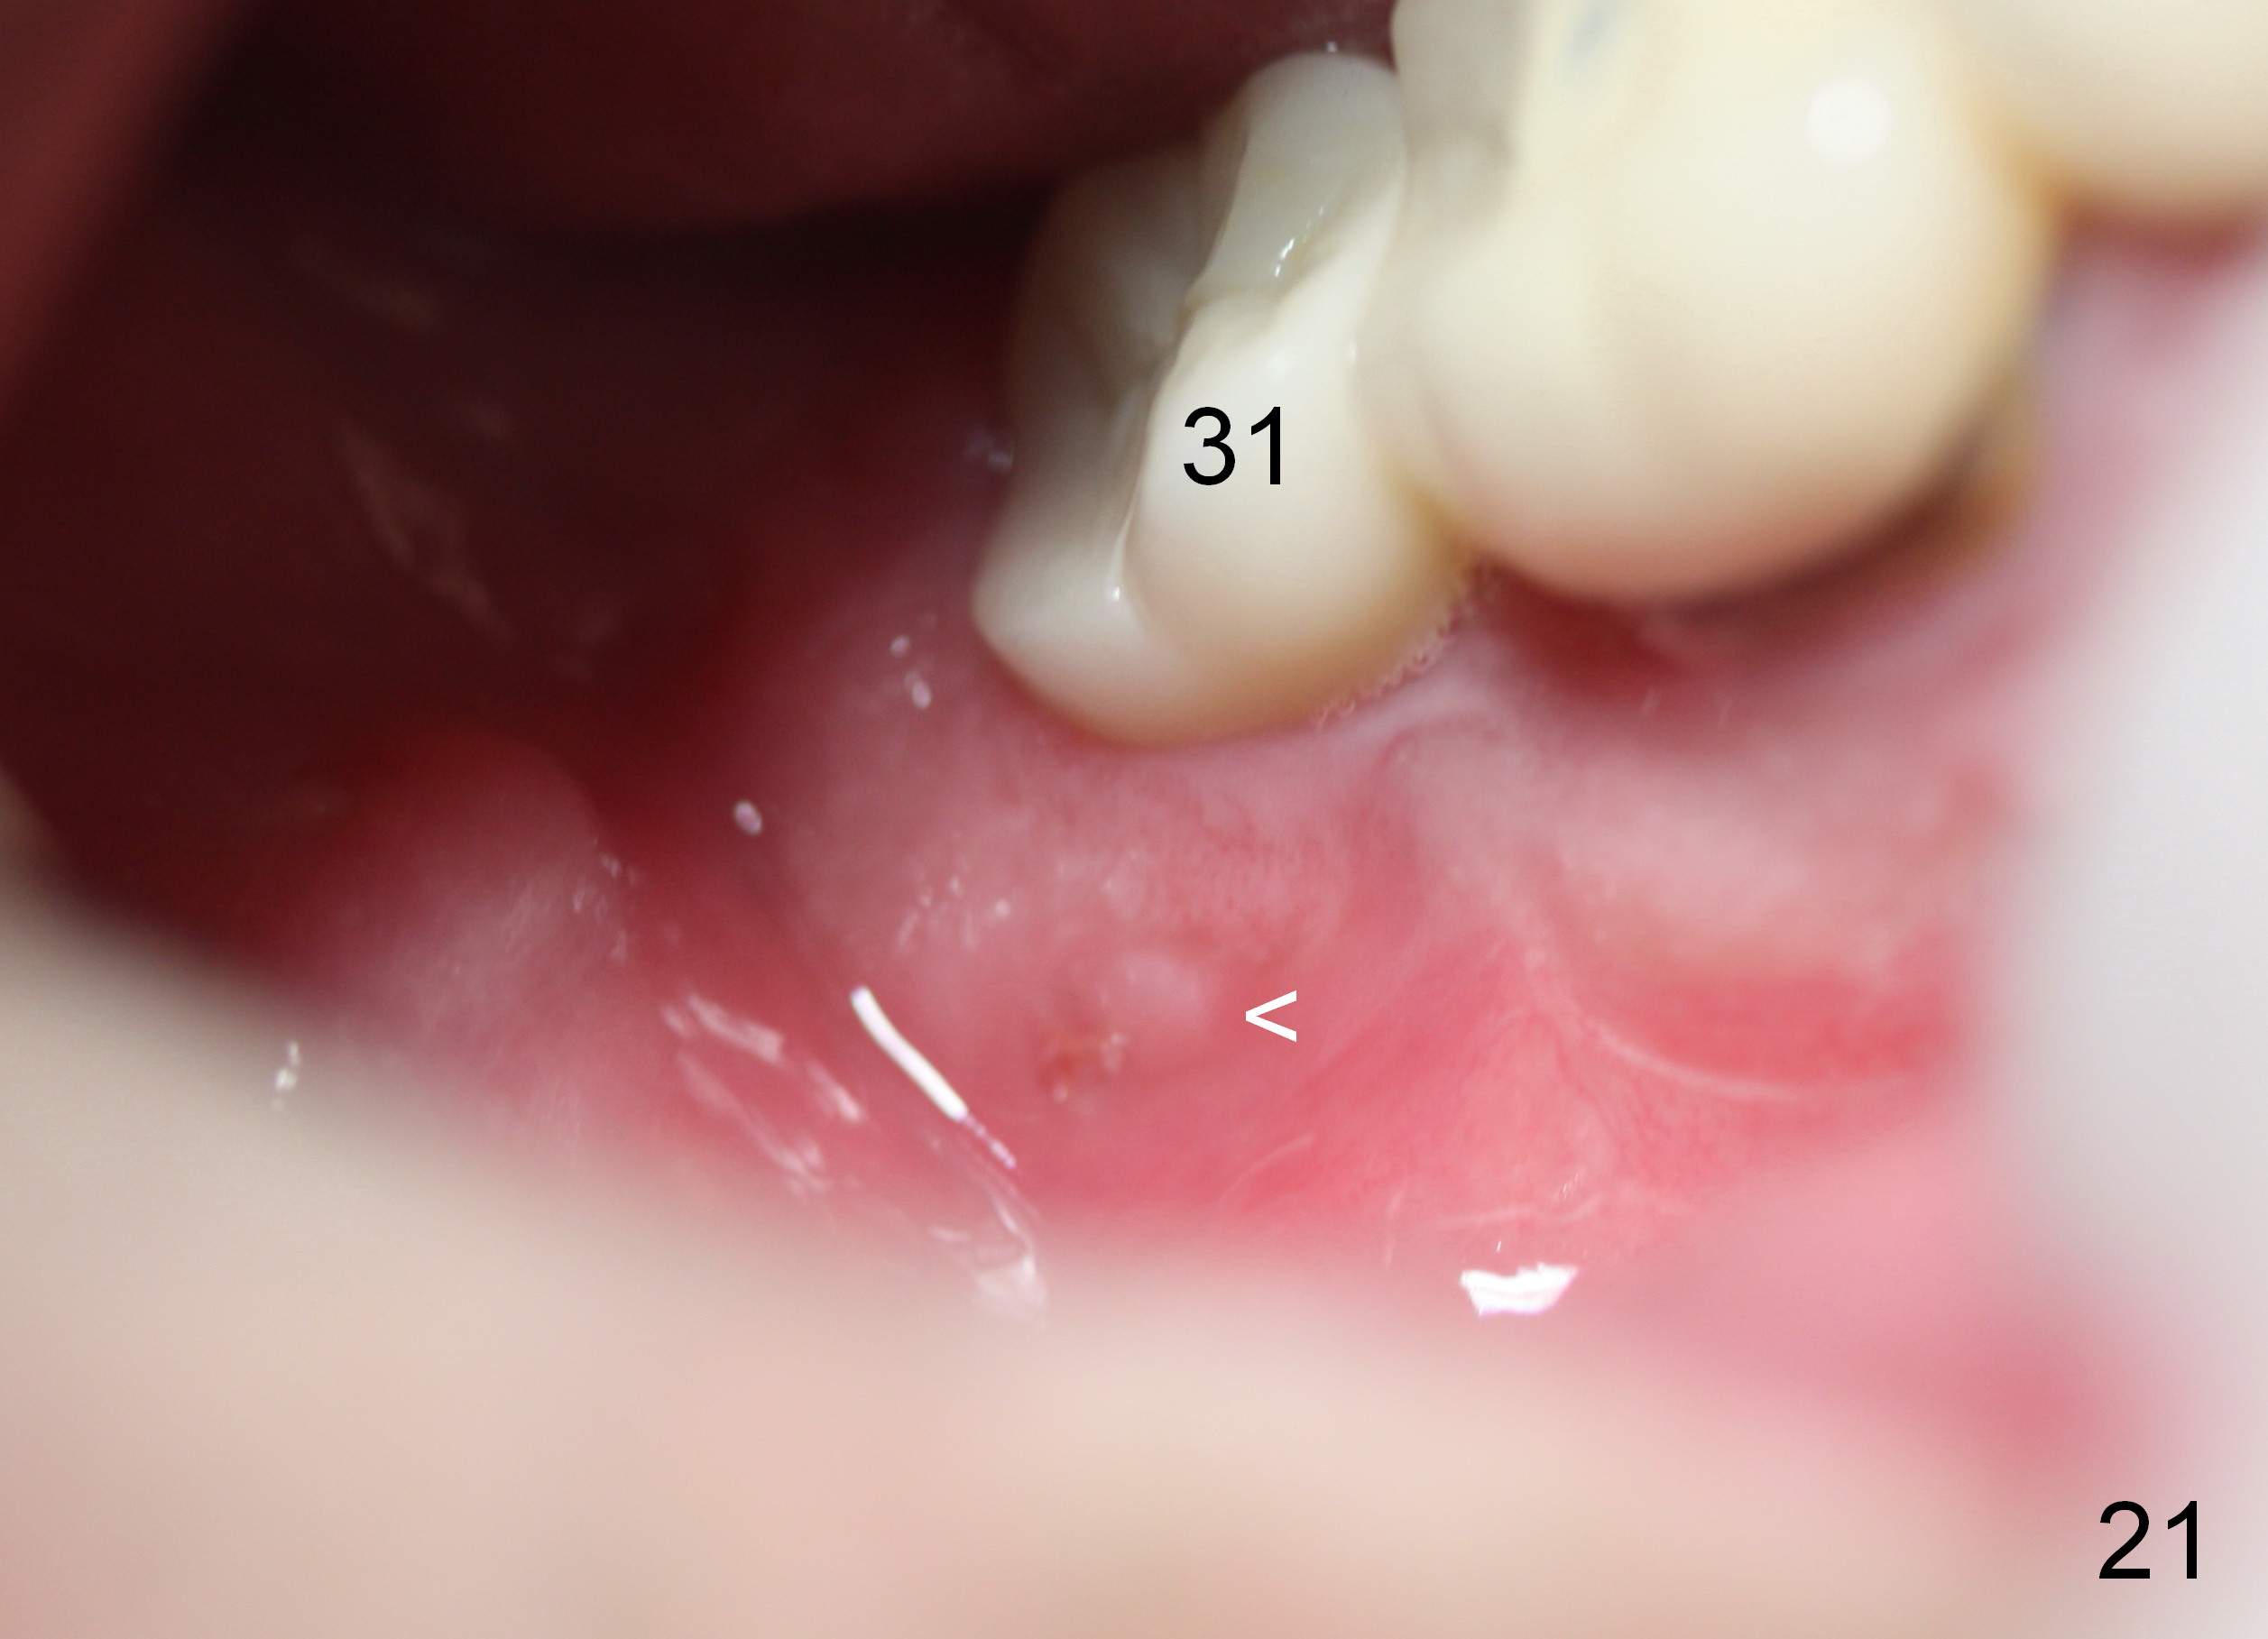

Four months postop, there is a sign of osteointegration (Fig.16 <). Graft particles migrate to the surface of the mucosa (Fig.17 <). A healing cuff is placed over the implant for preparation of restoration (Fig.18 H); graft particles are removed (<). Due to insurance issue, the restoration is yet to finish by 6 months postop (Fig.19 C: healing cuff); the cystic lesion appears to have been decreased concentrically (*). The bone density in the former cyst area continues to increase 14 and 32 months postop (Fig.20 A: abutment; Fig.22). Small piece of bone graft (<) is being extruded distobuccal to the #31 crown (C) asymptomatically 15 and 32 months postop (Fig.21,22).